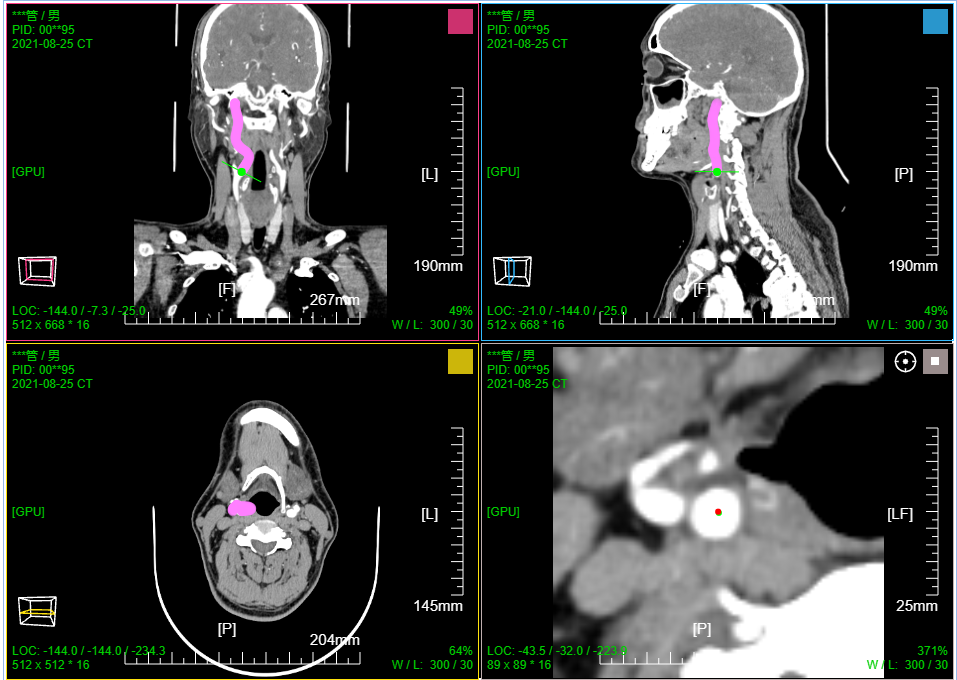

七、PET CT / MR融合功能操作和截图

二维融合,三视图显示;滚动滚轮三个序列窗口联动;

三维融合; 支持 MPR 9窗口视图;MPR+MIP 12窗口视图; (AXIS或CORO或SAGI)切片+MIP 6窗口视图

PT序列MIP窗口滚轮默认水平旋转; 其它序列MIP窗口滚轮默认缩放

PT序列MIP窗口左键默认缩放; 融合序列MIP窗口左键默认移动; CT序列MIP窗口左键默认旋转

点击MPR窗口右上角颜色块可AXIS轴位、CORO冠位、SAGI矢位切片切换

鼠标右键点击MPR窗口左下 切片位置指示器 可显隐十字交叉线; 左键点击MPR复位

鼠标左键点击MIP窗口左下 三维旋转状态指示器 可快速旋转到指定面; 右键点击三维旋转复位

PT序列MIP窗口拖动 "绿色X" 自动计算并定位最大SUV点位置并定位十字交叉线刷新显示MPR